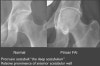

집게형 충돌(pincer impingement) 시에는 절구에 이상이 존재합니다. 정상 절구 모양은 앞으로 전굴(anteverted) 형태로서, 절구 뒤쪽륜이 앞쪽륜보다 더 가쪽에 위치합니다. 앞쪽 절구륜이 뒤쪽륜보다 더 돌출된 모양일 때 집게형 충돌이 생기며, X-ray로는 앞쪽벽이 뒤쪽벽보다 더 가쪽에 위치하는데 이를 'crossover sign'이라고 합니다.

MRI : Crossover sign